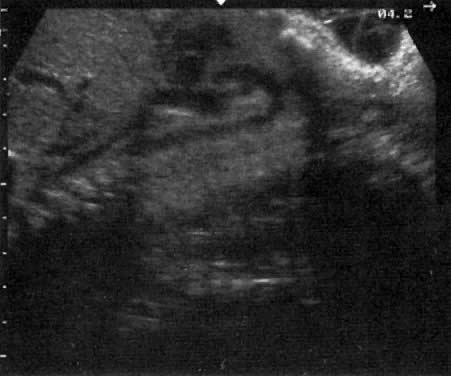

In most skeletal dysplasias, the first noticeable feature is short limbs (Fig. 31. Once this is established, a detailed survey of fetal anatomy is carried out to identify the specific dysplasia. Attention to the following areas is helpful: (1) facial abnormality, (2) cephalic size, (3) shortened radius, (4) segment of bone shortened, (5) small or barrel-shaped chest, (6) cardiac defects, (7) head size, (8) protuberance of abdomen; (9) fetal edema; and (10) demineralization of bone. The abnormal ultrasound findings in various skeletal dysplasias are listed in Table 16.